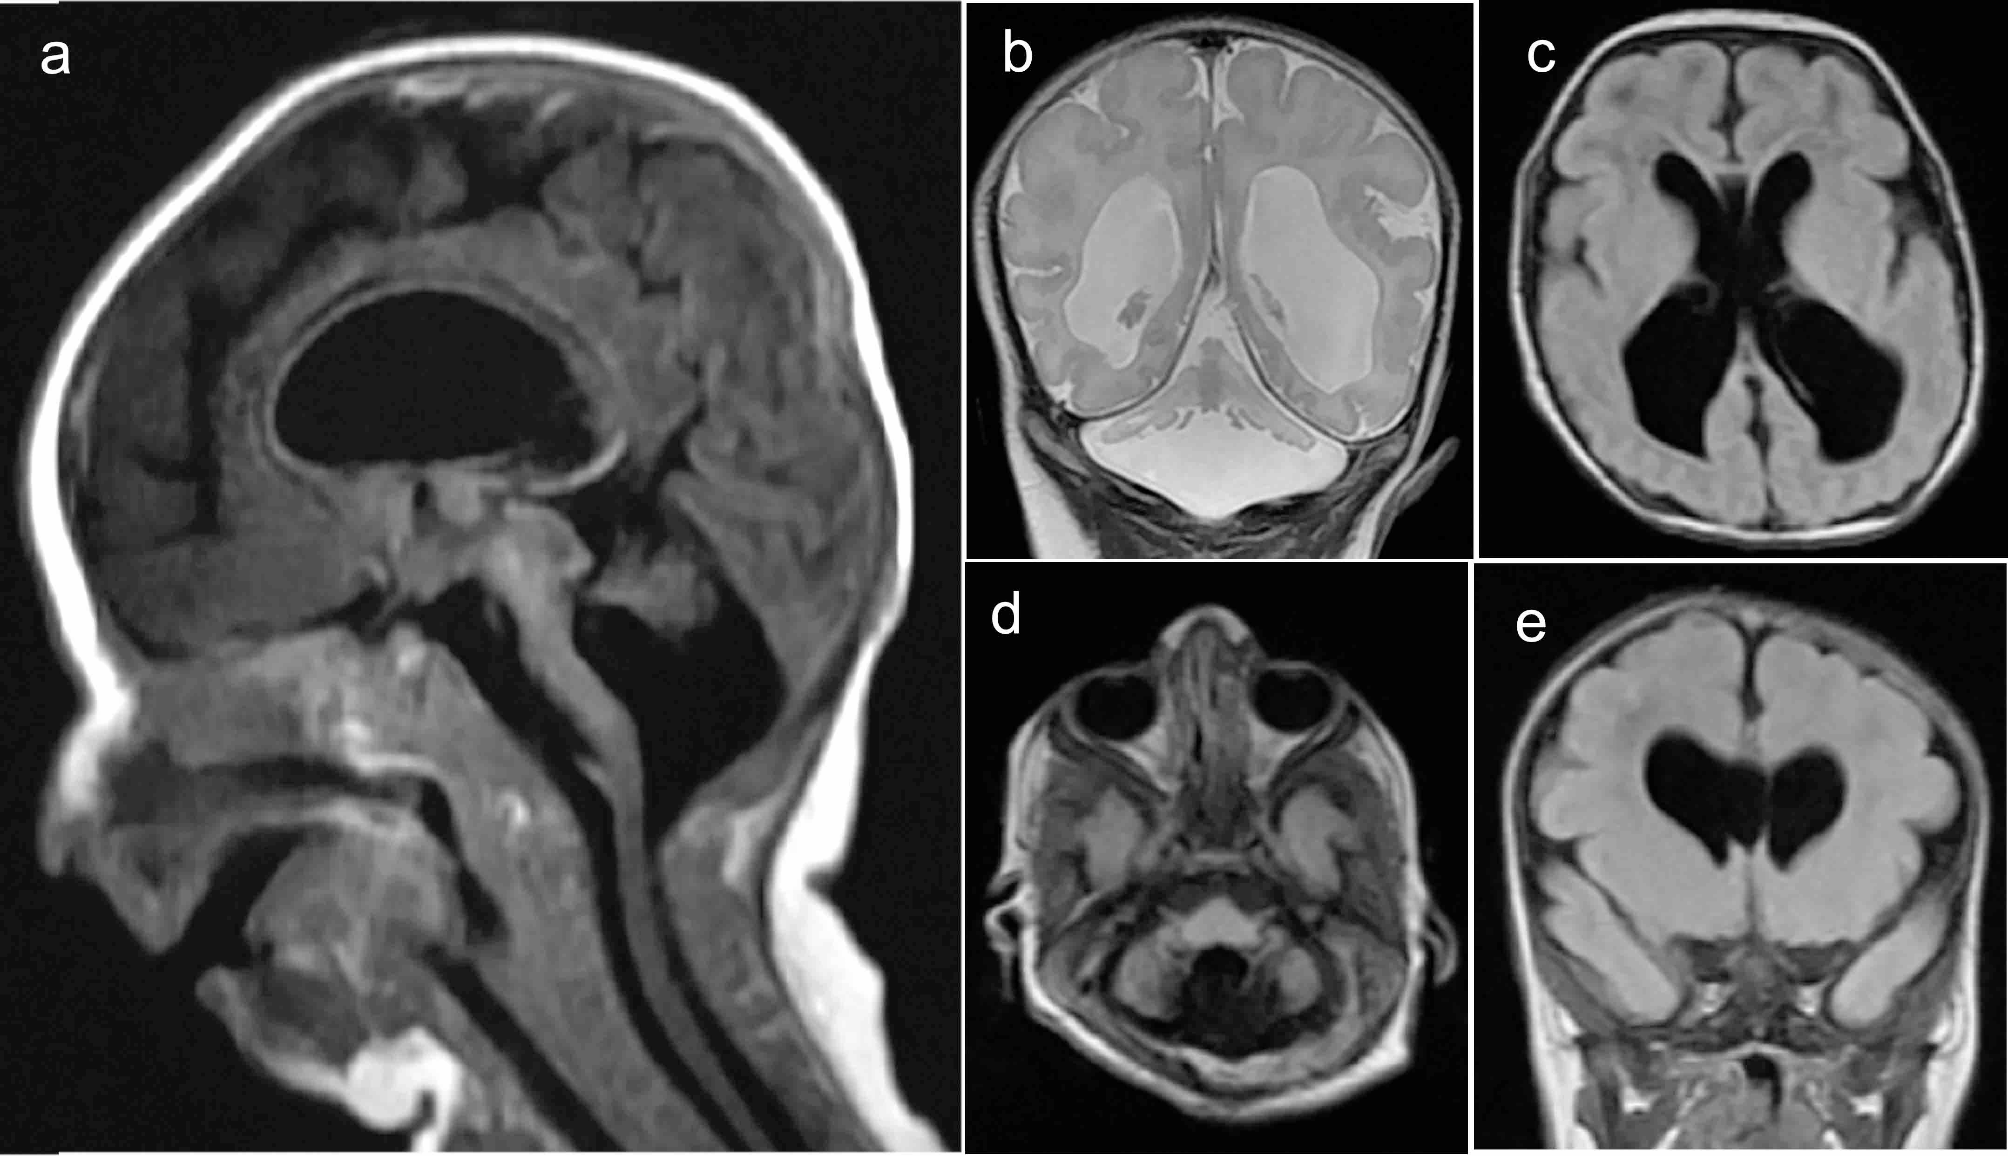

From: A homozygous variant in ARHGAP39 is associated with lethal cerebellar vermis hypoplasia in a consanguineous Saudi family